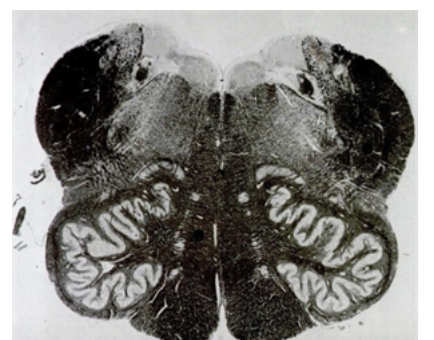

What brain stem cut is this?